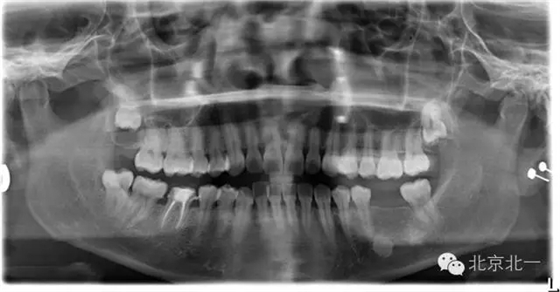

先看一例病例。頜骨內(nèi)單發(fā)高密度影像。是什么?能不能影響種植, 骨島是什么鬼?需要怎么處理?

如已經(jīng)證實(shí)骨島,是可以進(jìn)行種植牙。但是骨島和致密性骨炎不好區(qū)別。 因?yàn)橹旅苄怨茄兹绻M(jìn)行種植必將失敗,切記!切記!切記!

總結(jié):出絕招,如果遇到診斷不明確的骨島或者高密度影像, 最好的方式就是躲避, 不碰及它。

【口腔種植】致密性骨炎/牙骨質(zhì)增生/骨島如何鑒別?

頜骨三種高密度影像的鑒別

3)骨島:

概述:

主要和根尖型骨島鑒別,主要集中位于根尖區(qū)的骨島,

【CBCT表現(xiàn)】:

在CBCT上,根尖型骨島無低密度帶狀影包繞,與周圍骨質(zhì)分界清晰,具有特征性的毛刷樣邊緣,且其發(fā)生區(qū)域的牙根牙周膜影像連續(xù)、完整、不導(dǎo)致頜骨的膨隆。

右下頜C4根尖區(qū)課件一類圓形高密度影,與周圍骨質(zhì)分界清晰,C4牙周膜影像連續(xù)、完整,下頜骨未見膨隆。